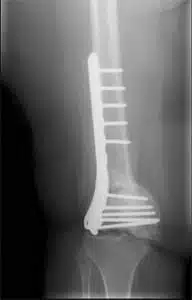

Post-traumatic arthritis